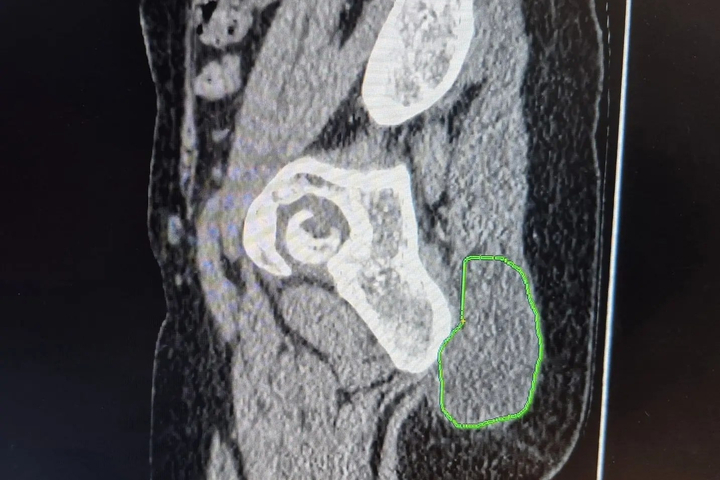

Результат оказался пугающим: после активного механического воздействия опухоль начала стремительно увеличиваться и достигла 10 сантиметров. Обследование в БГКБ (УЗИ, компьютерная томография и биопсия) показало, что «жировик» оказался злокачественным новообразованием, выросшим из жировой ткани.